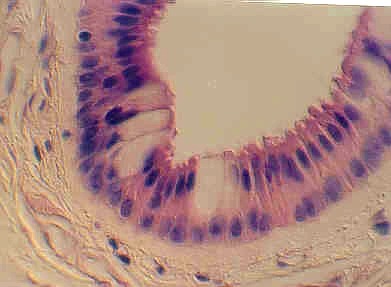

Below is another view of a large (excretory) duct of a salivary gland showing the mucin in Goblet cells after a special stain. What might be the advantages of an epithelium that has a basal cuboidal cell layer and an apical columnar cell layer?